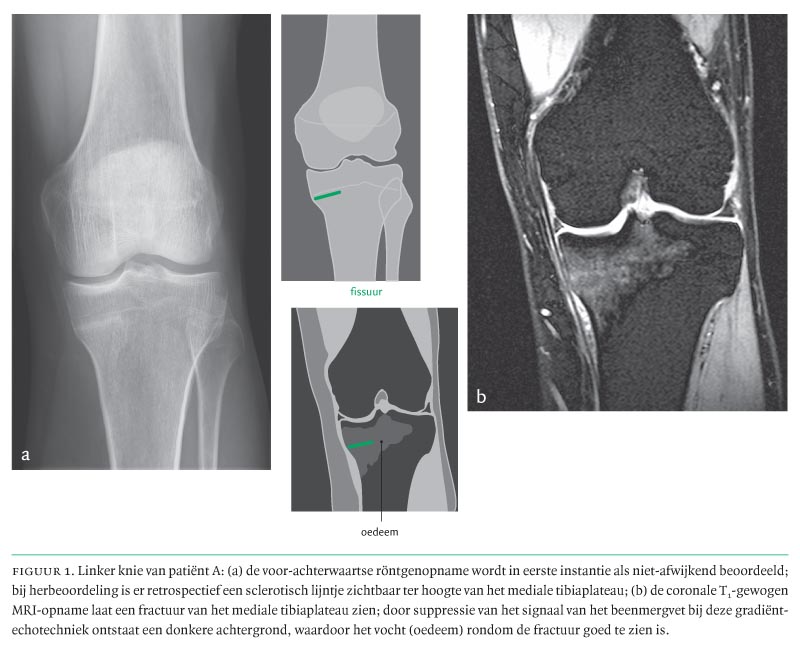

Drie Tevoren Gezonde Personen Met Een Vermoeidheidsfractuur Nederlands Tijdschrift Voor Geneeskunde